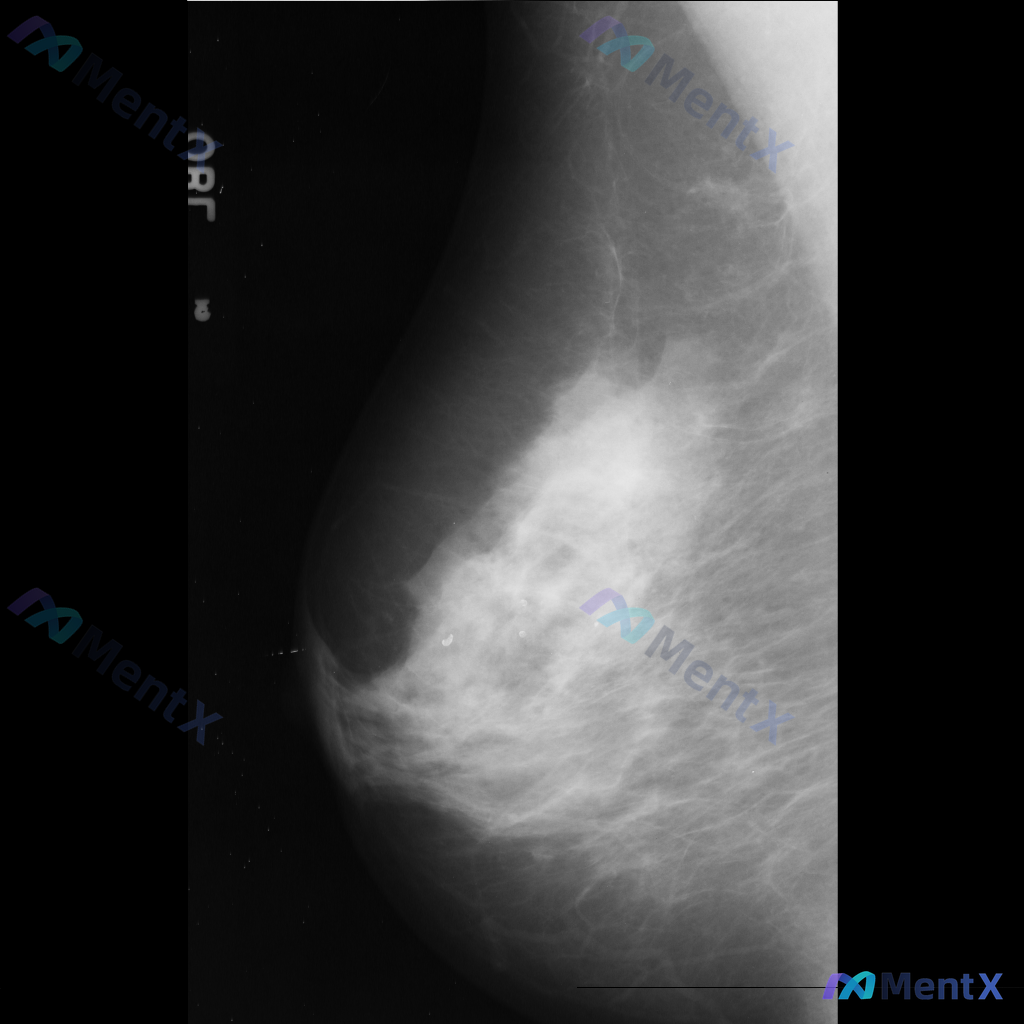

整理到一张乳腺钼靶影像的讨论资料,右乳可见一处病灶。 想先请大家看看:针对这张影像的异常表现,用什么术语描述最准确全面?另外结合征象,第一反应会往哪个方向考虑?

整理了一张乳腺钼靶影像的讨论资料,先和大家分享一下读片描述: 影像可见:不规则、高密度肿块/不对称致密影,伴有毛刺状边缘、结构扭曲和散在钙化。 目前考虑可能存在几种不同的异常方向,想先听听大家的第一反应——单看这组影像特征,你会先往哪种情况考虑? 也可以说说你最关注的是哪一点表现。